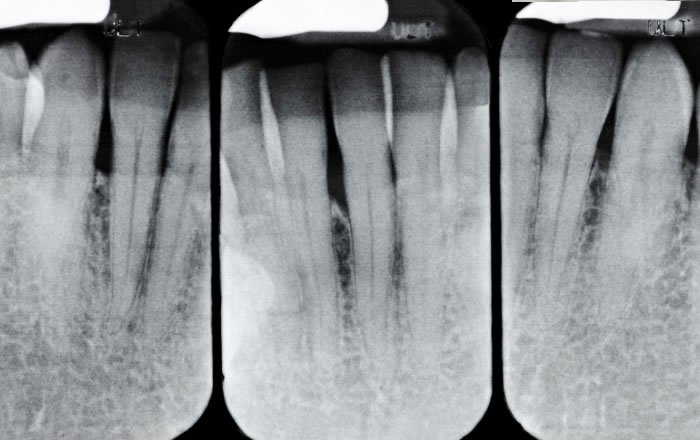

インプラント治療では、人工歯を支える顎の骨が健康であることがとても重要です。レントゲン写真やCTスキャンなどの画像診断を行い、骨の密度や量、歯茎の状態などを確認します。

この検査結果をもとに、インプラントを埋め込むベストな位置や角度について、入念に計画していきます。

インプラントオフィス大通では、レントゲンやCTも最新の設備をご用意し、患者さんの歯や顎の状態を検査・確認しています。